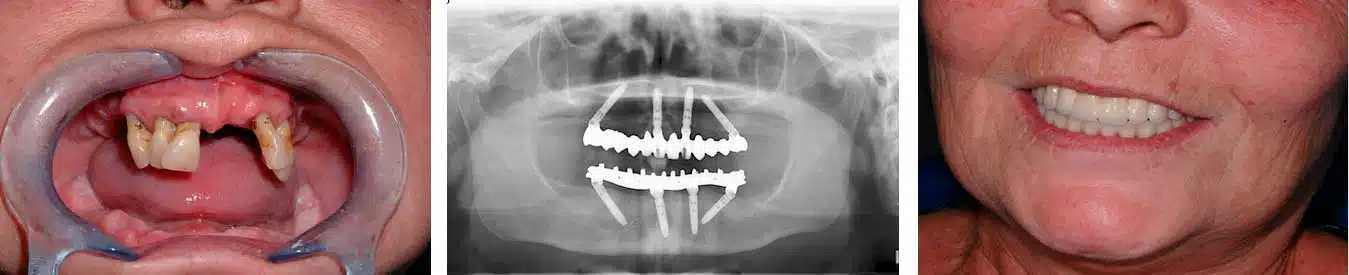

Rehabilitación fija sobre cuatro implantes

El concepto de tratamiento All-on-4; todo en cuatro, es una solución que proporciona una prótesis completa fija, el mismo día de la cirugía (superior, inferior o ambas).

Restauración de la arcada completa con solo cuatro implantes: dos implantes anteriores rectos y dos implantes posteriores inclinados hasta 45º. Pide cita gratuita para conocer el precio y decidir el mejor tratamiento en tu caso, sin compromiso alguno.

El tratamiento All-on-4® ofrece a los pacientes edéntulos (sin dientes) totales o parciales, una prótesis de arcada completa fija sobre cuatro implantes el mismo día de la intervención. Con el concepto de tratamiento All-on-4®, los pacientes que cumplen los criterios para carga inmediata, se pueden beneficiar también de una restauración acrílica inmediata sobre implantes, ya que una prótesis provisional se atornilla sobre los implantes inmediatamente después de la cirugía.